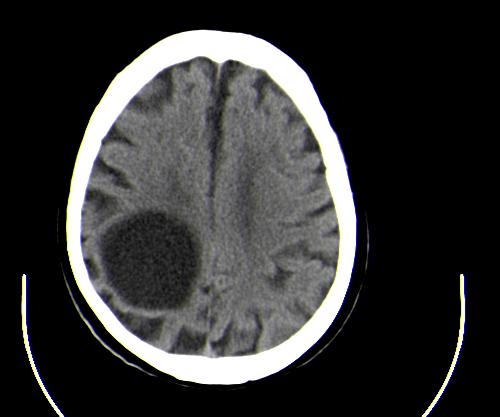

患者男性,67岁,头晕摔倒后来医院就诊,患者诉平时体健,否认有颅内病变史

定位:右侧脑室三角区扩大,呈球形,侧脑室颞角扩大,右侧脑室内占位:

定性:蛛网膜囊肿可能性大;

定位:右侧脑室三角区扩大,呈球形,侧脑室颞角扩大。

考虑:1、右侧侧脑室三角区室管膜囊肿?皮样囊肿?

2、脑萎缩。

神经上皮囊肿为先天性疾病,可发生在脉络丛、脑室内、脉络膜裂,少数位于脑质内,侧脑室三角区最为常见。按发生部位和囊壁的细胞学类型可有不同的命名。位于脉络丛者为脉络丛囊肿,常两侧同时发生。脑室内者为室管膜囊肿,多位于侧脑室三角区。脉络膜裂囊肿可以是神经上皮囊肿,也可以是蛛网膜囊肿。 囊肿呈脑脊液样低密度,边界清楚整齐。患者多无症状,有症状者多为头痛、癫痫发作。囊壁很薄,ct一般不能显示,囊壁无钙化。囊肿可有占位效应,表现为相应部位的脑室或脉络膜裂较对侧扩大,脑实质受压,一般不引起脑水肿。增强:囊肿及囊壁均无强化。

与蛛网膜囊肿的鉴别:蛛网膜囊肿好发于中颅窝、鞍上、半球、后颅窝、侧裂,脑室内少见,临床表现和影像学与神经上皮囊肿无明显差别。主要靠发病部位鉴别。